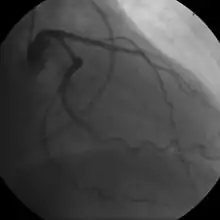

![]() | |

Illustration depicting atherosclerosis in a coronary artery | |